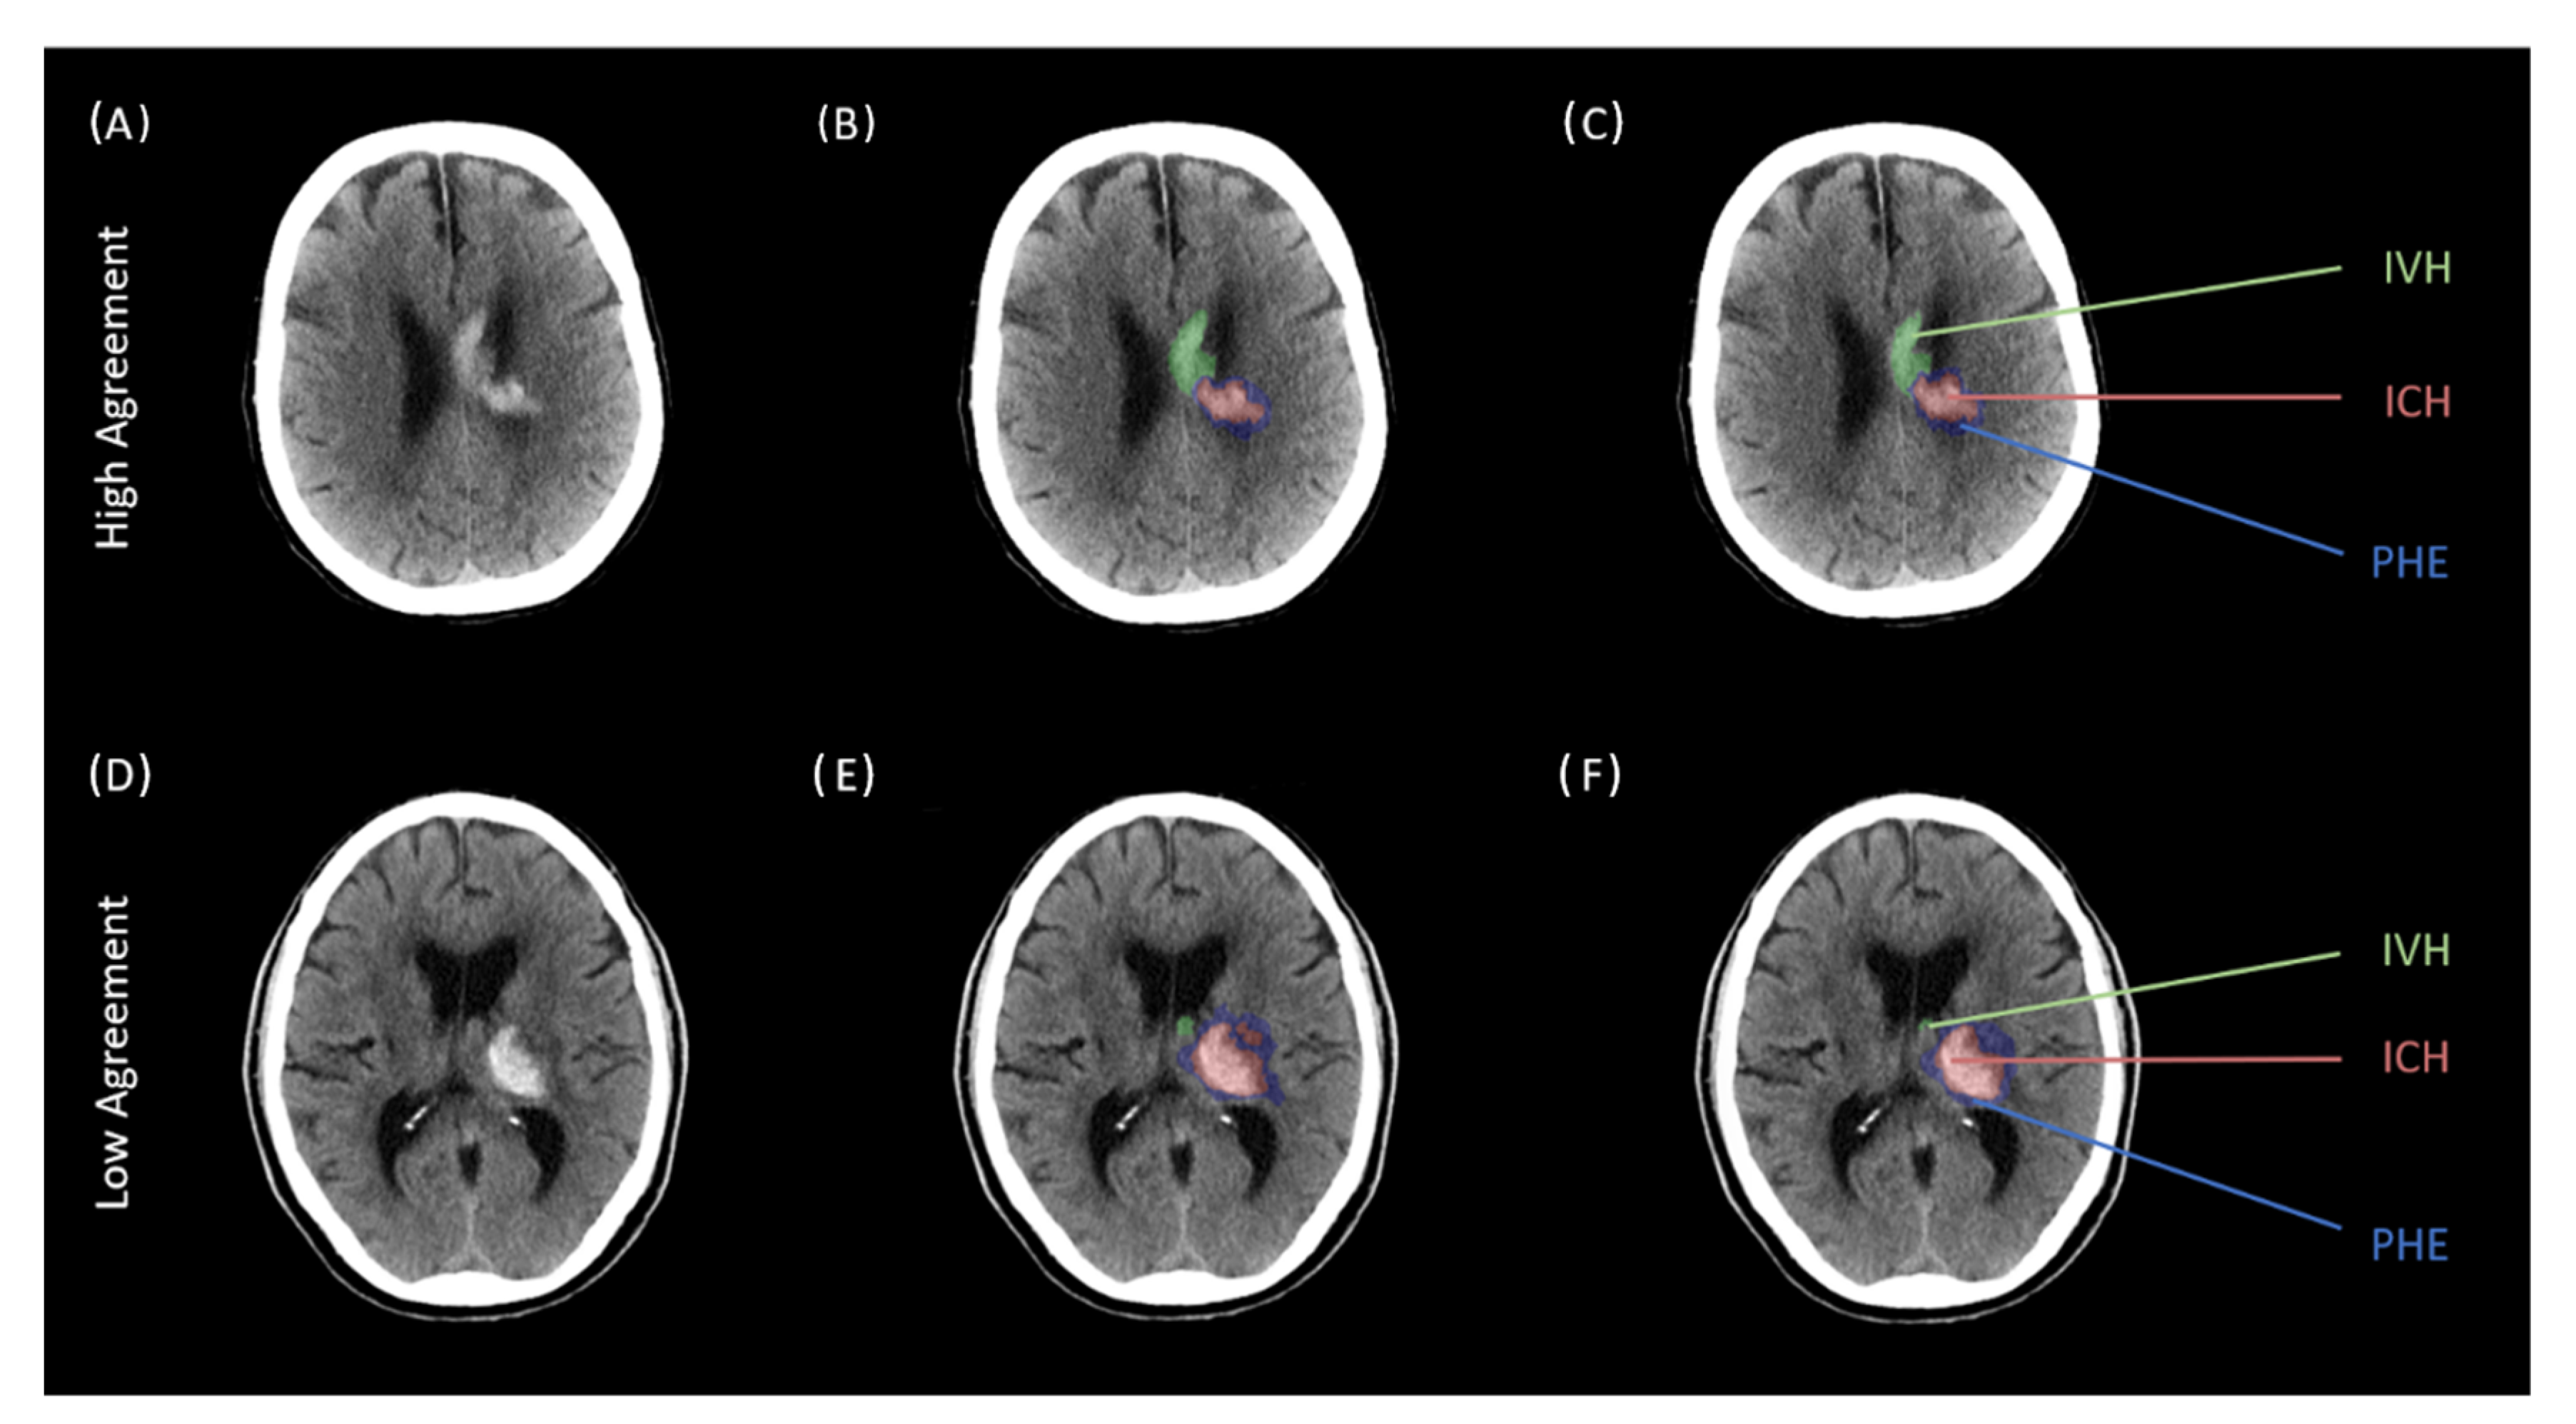

2.3. Image Analysis

3. Results